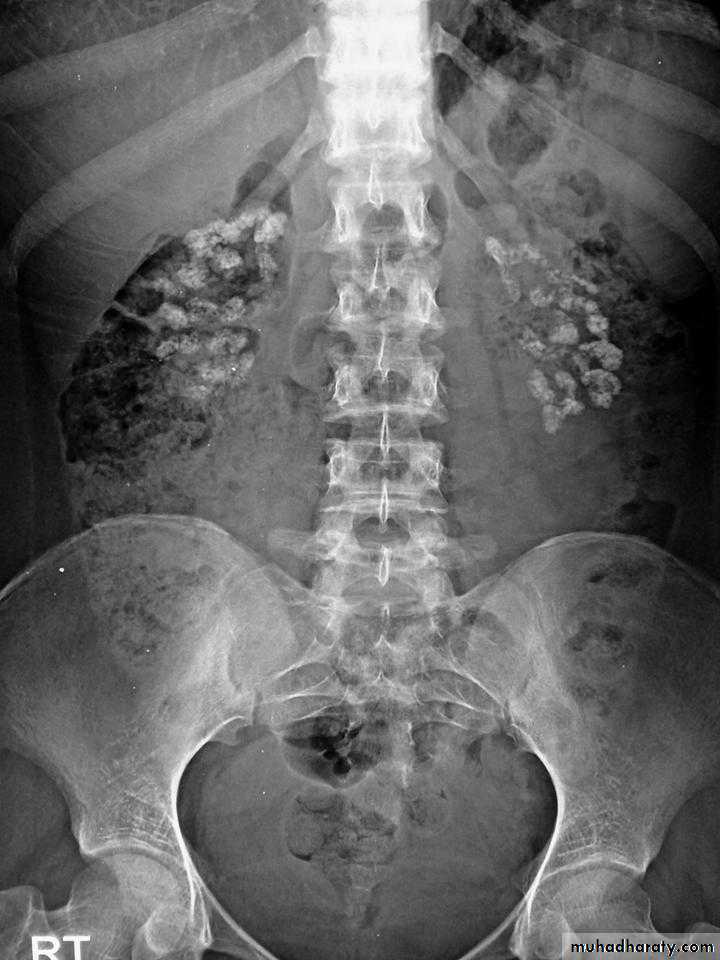

Primary hyperparathyroidism(Radiological features)

Characteristic changes on plane X ray are:

Demineralization, subperiosteal erosion and resorption of terminal phalanges

Pepper pot appearance of the lateral X ray of the skull

Scattered opacities within the renal outline (nephrocalcinosis)

renal stones

Soft tissue calcification affecting arterial walls, hands or cornea

Chondrocalcinosis